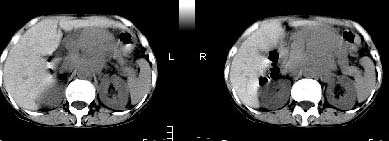

胰腺受压前移,胰管扩张,应为腹膜后占位,病灶密度不均,有低密度坏死区,强化扫描强化不明显腹腔干动脉受侵,考虑腹膜后恶性占位

从发病部位(腹主动脉周围)及增强方式(均匀轻度强化、少量坏死)和病变形态(较大、多结节形)符合腹膜后淋巴瘤,建议颈部病变活检。

我的第1诊断还是考虑是淋巴类病变1}。从病灶形态上看不是很规则,但其更向是多个结节的融和,其内有少许坏死,整个病灶的强化不是很明显,临近左恻肠间隔有增厚,2}我认为更重要的一点的是肠系膜有明显增厚呈片状。3}患者的脾脏不大其未见异常病灶。结合以上几点我首先考虑是转移性{但对此诊断我觉得不足之处;转移性的淋巴结肿大融合为什么没有坏死?}。{另外患者无大便习惯改变及血便,其发现右颈包块在今年过年无意发现}。以上是我的浅分析望各位战友继续讨论!谢谢!!

肝胃之间、肝十二指肠韧带,胰头后、腹主a周围,融合而成团块状影,包绕血管[腹腔干、肠系膜上动脉,腹主动脉],胰腺前移后缘分界欠清,与肝胃分界清,肿块未见明显强化,肝右叶后段小囊肿。

主动脉-胰腺间隙可见巨大分叶状软组织肿块影,包绕腹主动脉、腹腔干及其分支、腔静脉等大血管,增强呈无明显强化,临近脏器明显受压移位,增强示有分界。肝右叶可见局限性低密影,边缘清楚。

考虑腹膜后淋巴瘤。

影象诊断:考虑淋巴瘤待除外胃癌腹膜后淋巴结转移

讨论:首先看肠系膜和腹膜后的肿块我认为是多发融合的肿大的淋巴结。理由1大小不等的分叶,分布比较

自由。2其中的包绕的血管和周围少量的脂肪即所说的。

同时胃的影象表现和临床的不典型表现,所以我认为淋巴瘤,临床表现不支持胃癌